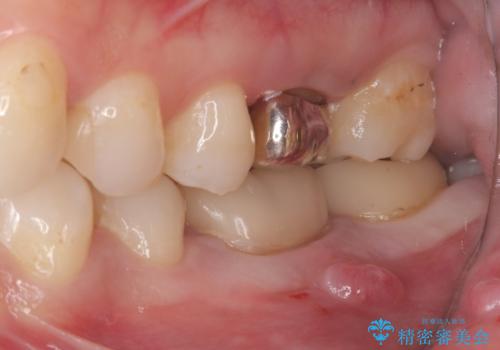

よく見ると歯冠部に咬合面から近心側にのびるヒビ(クラックライン)が入っているのが見えます。

咬合力によるヒビの部分に生じる歪みを軽減するため、クラウンを被せました。

「噛むと歯が鈍く痛む」を主訴に来院されました。

各種検査を行い、咬合面にヒビ(クラック)を認めました。

元々咬合面にレジンインレーが入っており、近心歯質が薄くなっていたことや、食いしばるクセを持っていることも、ヒビが入った要因の一つと考えられます。

咬合力によるヒビの部分に生じる歪みを軽減するため、ヒビを追えるところまで切削しCR裏層・支台歯形成を行い、一度仮歯に置き換え症状の緩和を確認し、CAD/CAM冠を装着しました。